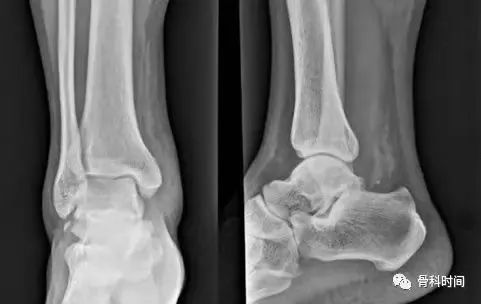

踝内翻损伤造成距腓前韧带距骨止点处撕脱骨折

30 岁青年女性,1 年前右踝首次发生崴脚,未行外固定,伤后右踝间断数次崴脚,双侧踝关节应力正位片测量距骨倾斜角,左侧为 0°,右侧 7°,右侧虽尚不能诊断踝关节不稳,但距骨倾斜角增大,对比对侧仍考虑为崴脚后未外固定所致。